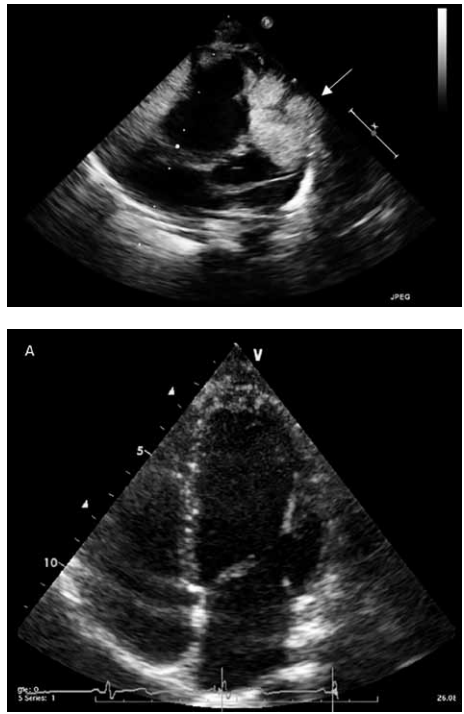

A primeira figura é uma foto de um ecocardiograma realizado em um recém-nascido com tumores múltiplos na parede lateral do ventrículo direito sem causar obstruções. A segunda figura é uma foto de um ecocardiograma realizado na mesma criança aos quatro anos de idade.

Qual o diagnóstico mais provável?